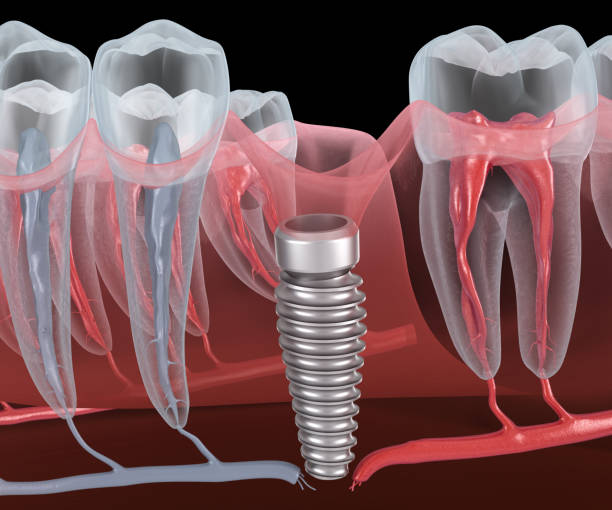

| آیا میتوان بعد از عصب کشی دندان ایمپلنت انجام داد؟ | بله، اگر دندان عصب کشی شده قابل نگهداری نباشد، میتوان آن را کشید و ایمپلنت انجام داد. |